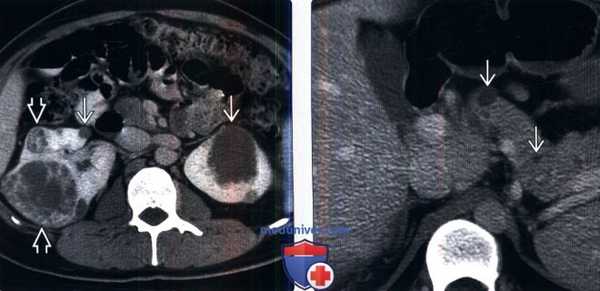

(Слева) КТ с контрастированием, аксиальная проекция: у пациента с болезнью Гиппеля-Линдау выявлены двусторонние кисты почек и множественные сложные кистозные объемные образования с контрастируемыми узелками и перегородками, что позволяет предположить кистозный ПКР. Кисты почек и ПКР - распространенные висцеральные проявления болезни Гиппеля-Линдау.

(Справа) КТ с контрастированием, аксиальная проекция: у данного пациента визуализированы множественные кисты поджелудочной железы.